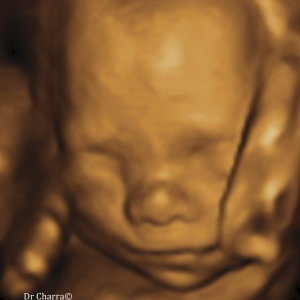

Suivi de votre grossesse avec réalisation des échographies recommandées, Prise en charge des IVG medicamenteuses (en lien avec la maternité de Beaune), infertilité, prise en charge des douleurs pelviennes (endométriose par exemple)

Diplômée en Echographie foetale et Gynécologique

Diplômée en Médecine Foetale

Agrément National pour la réalisation des échographies du Premier Trimestre de grossesse

Membre du Collège d'Echographie Foetale Français (CFEF)